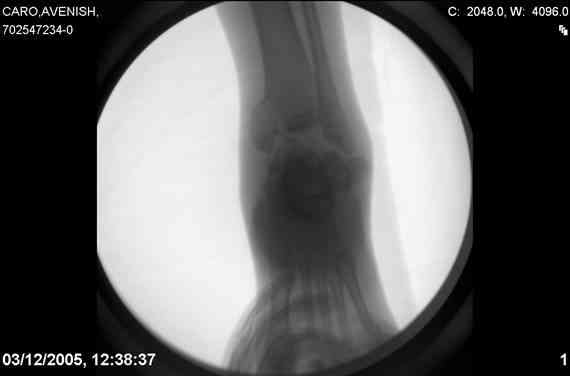

ya by popytalsya sobrat talus anatomichno,seichas pozdno operirovat iz za oteka,po etomy distrakziya apparatom budet optmalna.Posyalu vam podobyai moi sluchai.

14 years old girl

Fall from height ( 3rd floor)

Compressed fractures of L1-L2

Fx of orbital bone

Mark, судя по снимкам в день поступления произведен А.В.Ф., а остеосинтез ч-з какое время произведен?, остеосинтез произвели открытым способом?( на снимке п/о рубцы).

aparat postavlen v den postupleniya,rastaynuli, vpravili zakryto naskolko vozmoghno, a kogda otek spal sdelali otkrytoe vpravlenie.Teryat tut nechego, moghno tolko uluchshit.